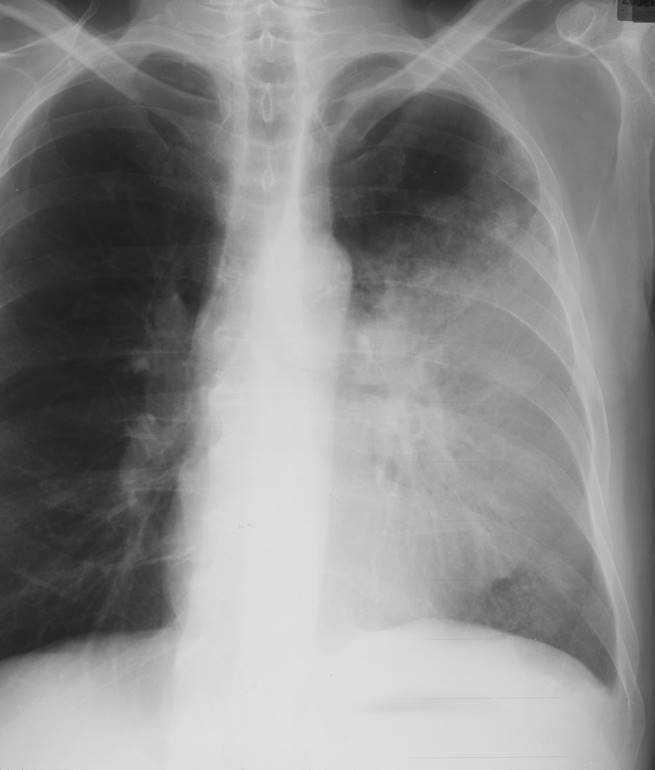

What do you see here?

Silhouette Sign, loss of defined heart border on left side